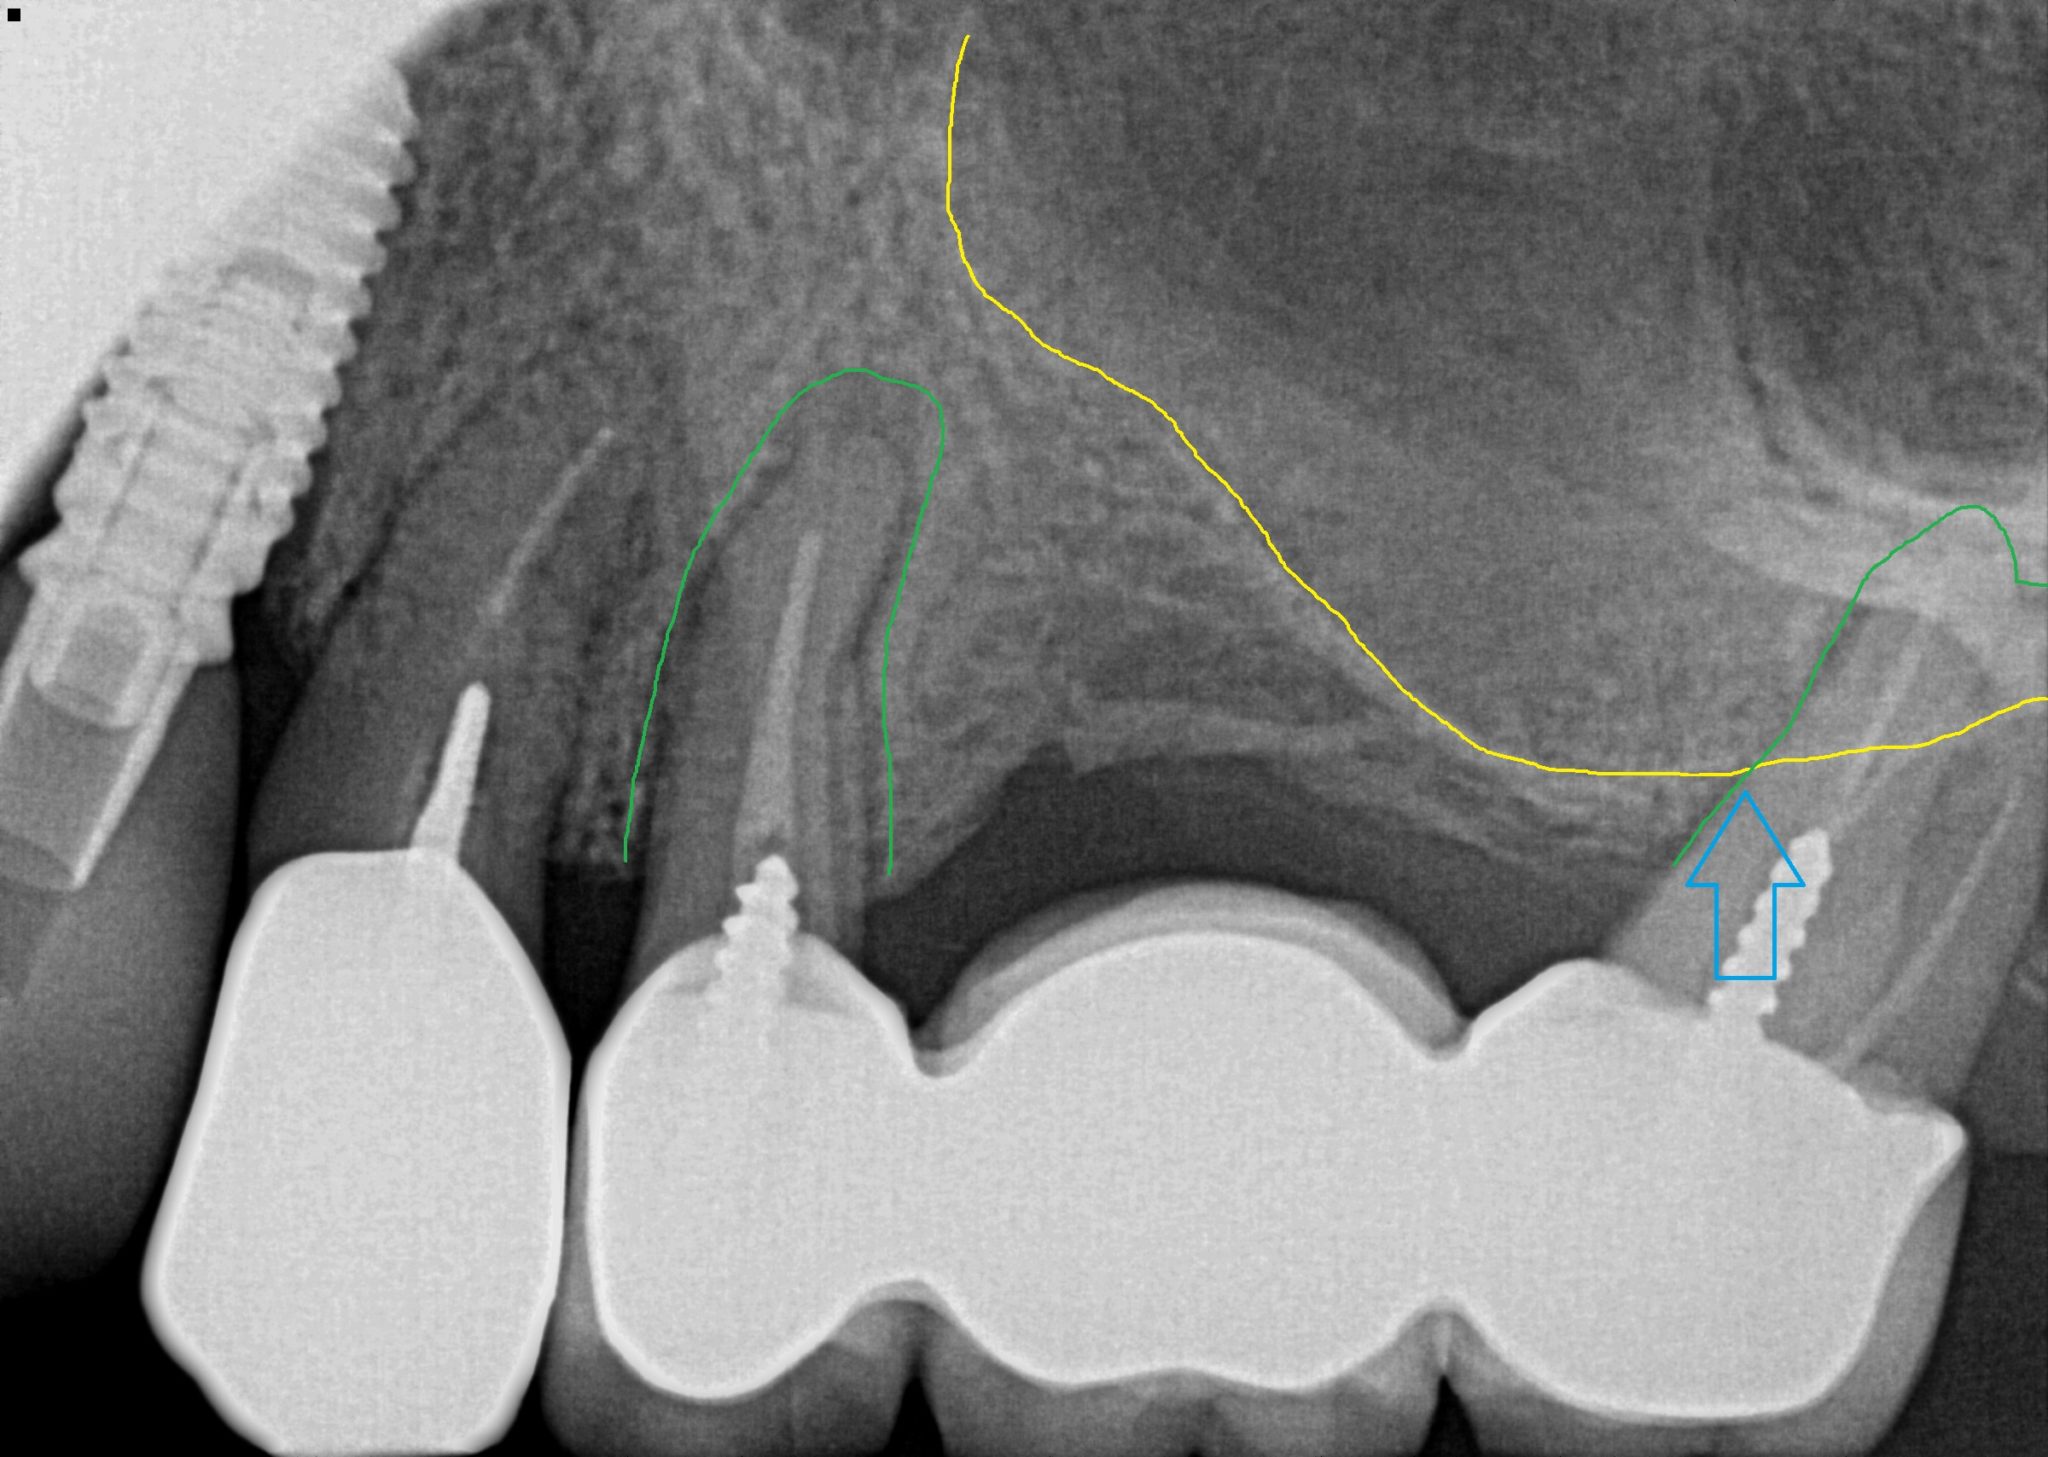

From www.joms.org

Endoscopic Surgical Treatment of Chronic Maxillary Sinusitis of Dental Tooth Extraction From Sinus Learn about the procedure, risks, and safe. Get expert advice on safe tooth extraction with roots in the sinus cavity. Sinus perforation after a tooth extraction is a potential complication that can occur during the removal of upper teeth, particularly molars and premolars. Discover essential insights on tooth extraction when roots are in the sinus cavity. Sinus perforation is a. Tooth Extraction From Sinus.